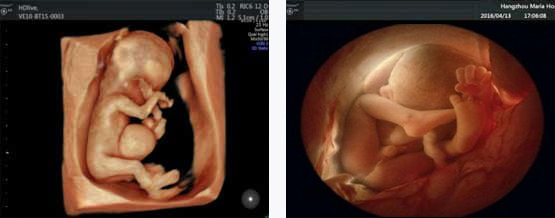

四维彩超能排查遗传性综合征等胎儿早期疾病。多角度观察宫内胎儿的生长发育情况,为早期诊断胎儿先天性体表畸形先天性心脏疾病提供科学依据。

四维彩超能够直观、立体地显示人体器官的三维结构以及动态,实时地观察立体结构,被广泛用于检查胎儿发育状况,立体观察胎儿在子宫内发育情况的同时,还能够清晰显示胎儿在子宫内的动态,让准爸妈们一起观看宝宝在妈妈肚子里的动作、神态,还可将这个过程制作成光碟保存,让宝宝能够拥有完整的0岁相册,留下珍贵的纪念。

四维彩超检查能够多角度观察胎儿在子宫内的发育状况,同时能够为早期诊断胎儿先天性体表畸形、先天性心脏疾病提供准确的科学依据。

一般情况下四维彩超的检查时间是孕22-28周,这段时间检查,胎儿大小适合,羊水适中,胎儿活动度大,体表也比较丰满,有利于胎儿四维超声成像和畸形筛查,是合适的检查时期。